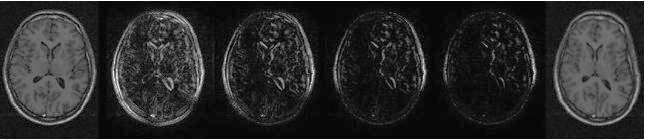

The idea is illustrated in Figure [*]. Instead of taking the sum-of-squared-differences between corresponding pixels, the minimum absolute difference between each pixel in one image and the values in a neighbourhood around the corresponding pixel is used. This is less sensitive to small misalignments, and provides a better-behaved distance measure. The tolerance for misalignment is dependent on the size of the neighbourhood ($r$), as is illustrated in Figure [*].

Figure: calculation of a shuffle difference image. Note that this diagram shows the symmetric calculation, whereas in experiments we use an asymmetric (one-way) calculation.

Image brains_shuffle_symmetric-revised